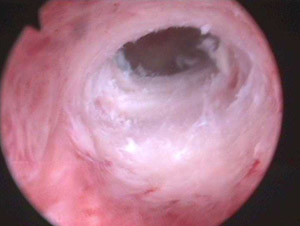

德 国一体化宫腹腔镜手术系统+4D微环境术是用于子宫腔内检查和治疗的内窥镜。了解致病因素,同时对异常情况做手术治疗。

德国一体化宫 腹腔镜手术系统+4D微环境术是在密闭的盆、腹腔内进行的手术。摄像系统在良好的冷光源照明下,通过连接到盆、腹腔内的腹腔镜体,将盆、腹腔内的脏器 摄于监视屏幕上,手术医师在高科技显示屏监视、引导下,于腹腔外操纵手术器械,对病变组织进行探查、电凝、止血、组织分离与切开、缝合等操作。